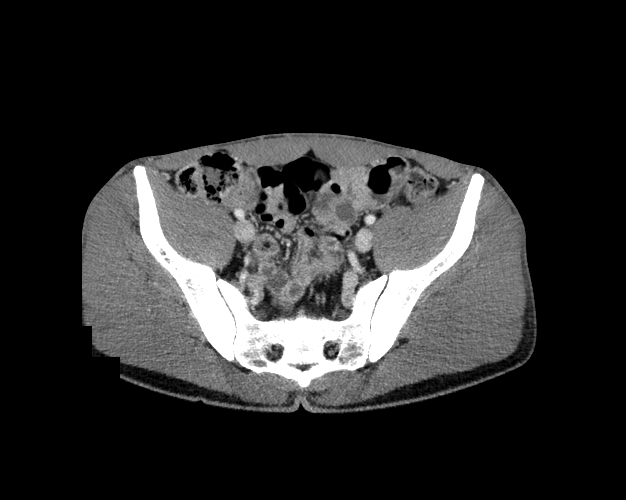

Pelvis

Covers pelvic MRI anatomy.